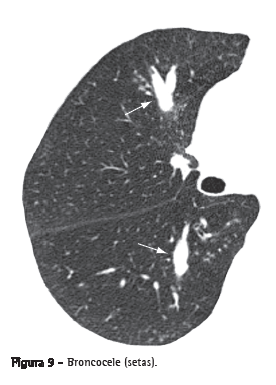

Broncocele

Dilatação brônquica com retenção de secreções (impacção mucoide), geralmente causada por obstrução proximal, que pode ser congênita (por ex.: atresia brônquica) ou adquirida (por ex.: aspergilose broncopulmonar alérgica).(21) A broncocele apresenta-se como uma imagem tubular ou ramificada que se assemelha a um dedo de luva (Figura 9). Na TC, pode-se observar, em casos de atresia brônquica, uma redução da atenuação do parênquima distal à lesão.